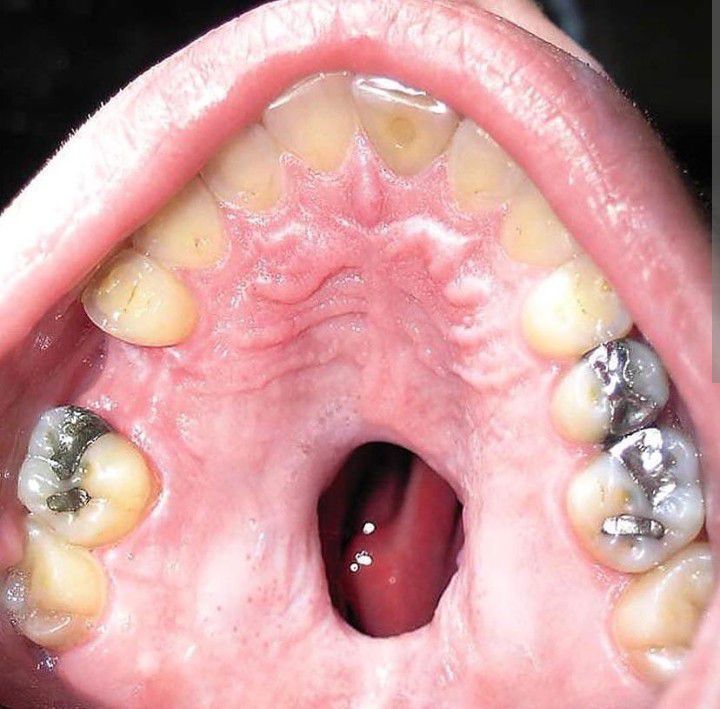

A healthy 25-year-old man presented to the surgical clinic with a hole in the roof of his mouth that allowed nasal regurgitation of food when he ate. The hole had been present for a year, and he requested surgical correction. The patient reported a 5-year history of nasal COCAINE use from which he had recently abstained. Physical examination revealed a large perforation of the nasal septum and midline palate. Local complications of intranasal cocaine abuse include chronic rhinitis, sinusitis, epistaxis, ossification or necrosis of the nasal septum, and in rare cases, palatal perforation. Use of cocaine, a potent vasoconstrictor, can lead to ischemia, necrosis, and ulceration, as seen in this case. Other causes of palatal perforation to consider include infection (syphilis, tuberculosis, or fungal infection), Wegener's granulomatosis, sarcoidosis, neoplasms (salivary or squamous cell), and midline lethal granuloma, a type of T-cell lymphoma. After consultation, the patient did not return for follow-up. By: https://www.instagram.com/p/CdLY6FgjJVN/?igshid=YmMyMTA2M2Y=